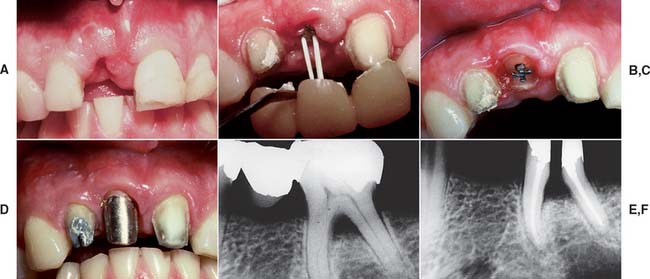

Because of extensive caries or periodontal disease, removal of a tooth may be more sensible than endodontically treating it, although a severely damaged tooth occasionally can be restored after orthodontic repositioning or root resection (Fig. 12-1; see also Fig. 16-7). This should be done if loss of the tooth will significantly jeopardize the patient’s occlusal function or the total treatment plan, particularly if dental implants are not an option. When the decision is made to treat the tooth endodontically, consideration must have been given to its subsequent restoration. Before being restored, teeth that have been endodontically treated must be carefully evaluated for the following1:

Fig. 12-1 A to D, A severely damaged tooth can sometimes be retained after orthodontic extrusion (see Chapter 6). E and F, Plaque control around periodontally compromised teeth may be improved after hemisectioning (see Chapter 5).

(E and F, Courtesy of Dr. H. Kahn.)